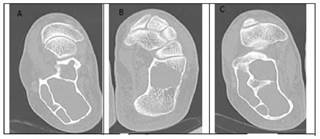

Our study involved the processing of bone CT images, so as to identify the region of bone cancer and perform a 3D evaluation. Axial raw CT images containing healthy and bone tumors are presented in Figures 2 and 3.